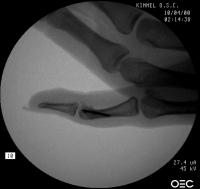

Case 2. Mass developing after a lateral dislocation of the proximal  interphalangeal joint of a 34 year old woman.

Radiographs were consistent with either a united collateral ligament avulsion fracture or ossiification of a parosteal hematoma.